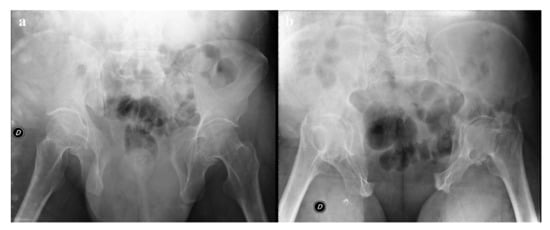

Figure 9. Plain radiography. The outlet view (a) and the inlet view (b) show a 5.2 cm diastasis of the pubic symphysis and anterior widening of the left-side sacroiliac joint. These findings have to be quickly reported to allow prompt treatment.

Plain radiography is also important in the follow-up of pelvic fractures, by performing anteroposterior and oblique outlet and inlet projections (Figure 9). The outlet view is obtained by directing the inclination of the x-ray beam tilt from the feet at an angle of 35° to the x-ray table, and it allows detection of sacral fractures and craniocaudal dislocations. The inlet view is obtained by directing the inclination of the X-ray beam tilt from the head at an angle of 35° to the X-ray table, and it allows detection of any anteroposterior displacement of the sacroiliac joint or any rotation of a hemipelvis [17,36].